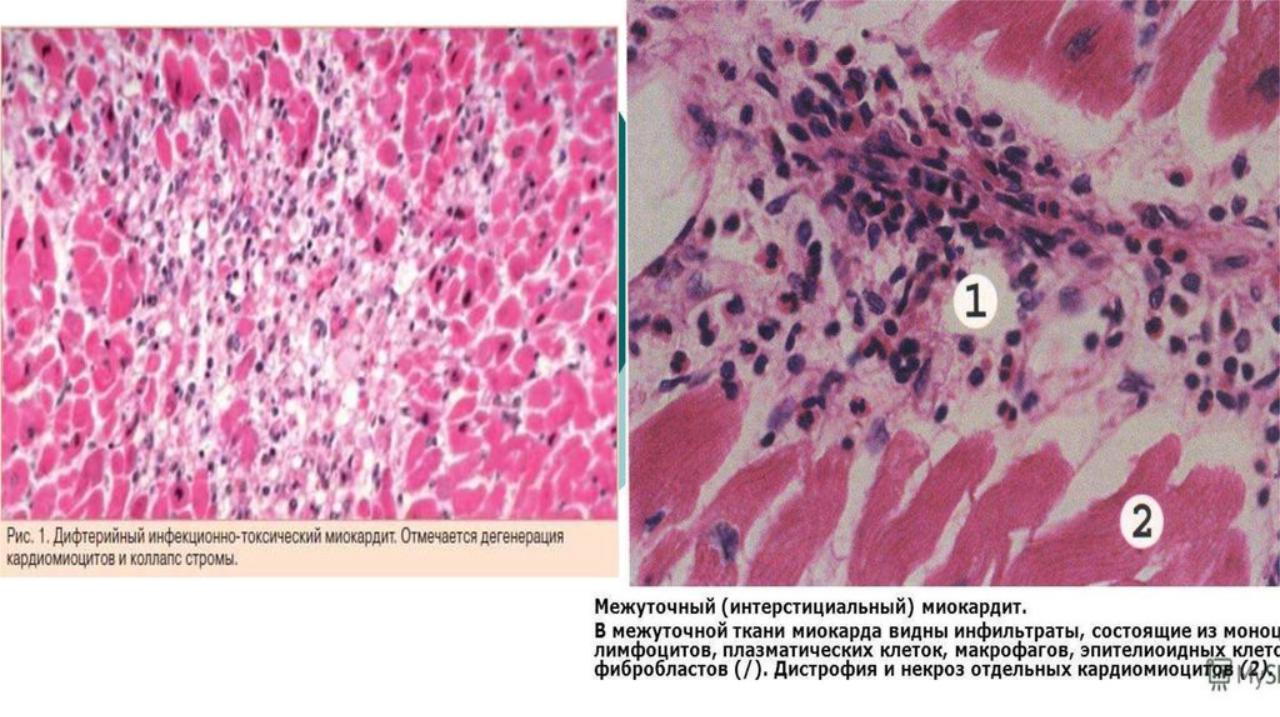

Межуточный миокардит: гистологические исследования